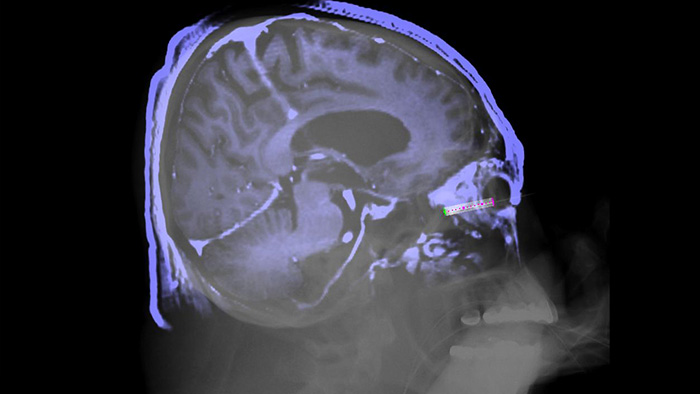

La solution SmartCT Soft Tissue offre une technique d’acquisition CBCT (Cone Beam CT) complétée par un guidage pas à pas. Les outils avancés de visualisation et de mesure 3D sont tous accessibles sur le module à écran tactile, depuis la table. Pour vous aider dans le processus d’acquisition des images CBCT dès la première fois1 et pour rationaliser votre flux de travail, vous êtes guidé à travers les étapes clés.